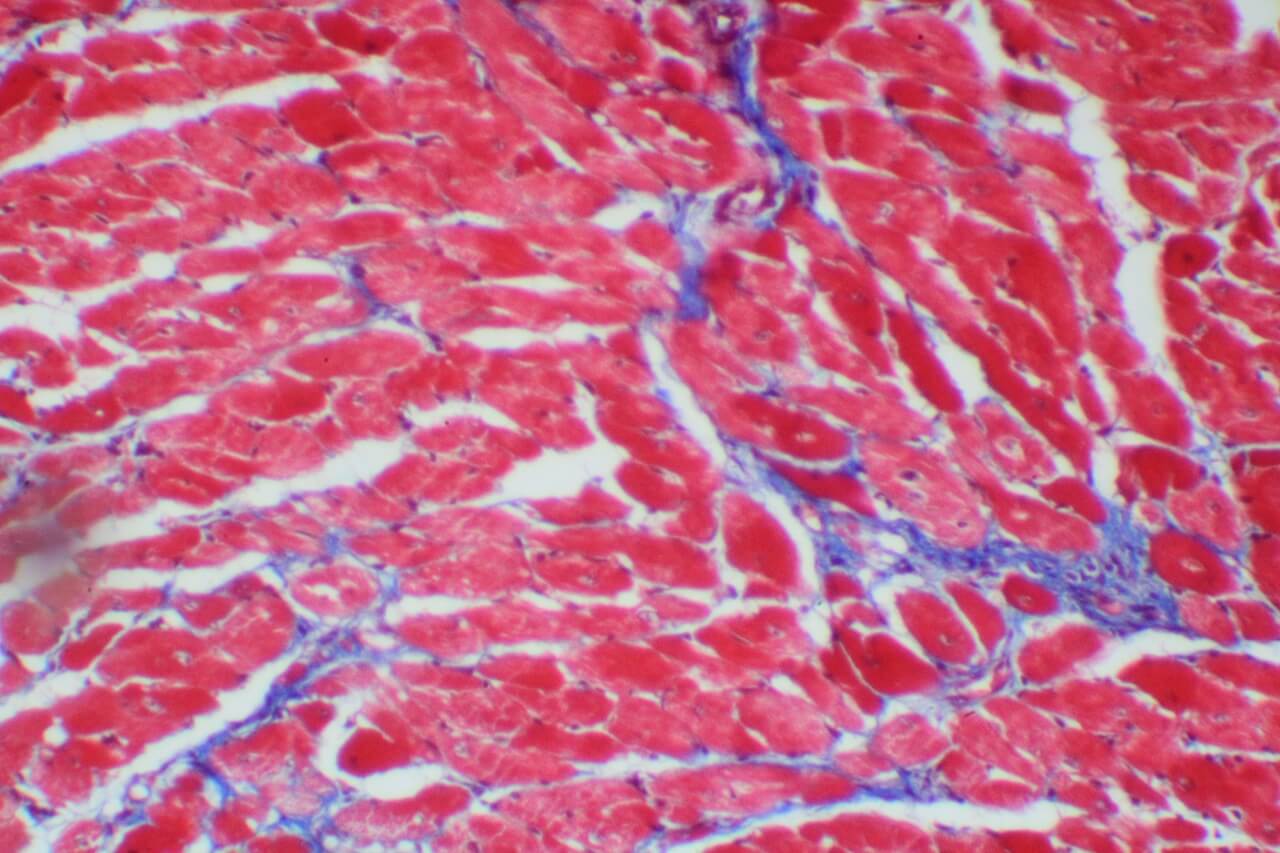

特殊染色

By

立众小編1號

2021-07-01